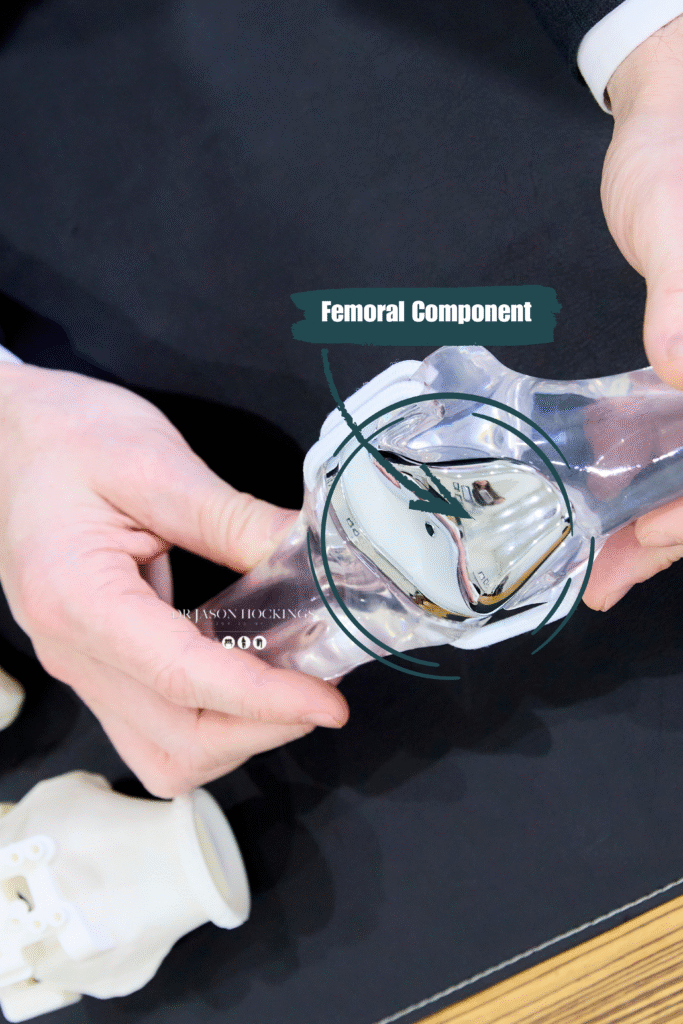

FEMORAL COMPONENT

A metal cap that covers the end of the thigh bone (femur). This part is shaped to allow smooth bending and flexing of the knee.

Dr Hockings primarily uses a medial pivot implant, (GMKSphere). This design differs from traditional implants by mimicking the knee’s natural movement more closely. The medial pivot allows the inner (medial) side of the knee to act as a stable pivot point, while the outer (lateral) side moves more freely, similar to how a healthy knee works.

- Cobalt-chromium or titanium alloy for the femoral and tibial components, chosen for strength and wear resistance